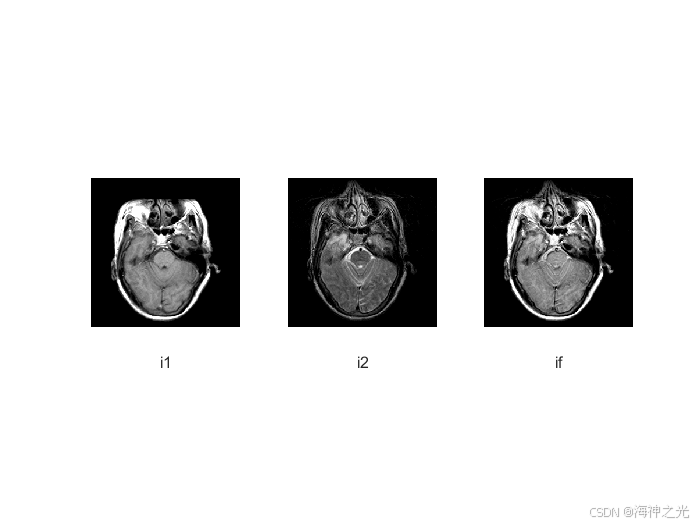

⛄三、运行结果